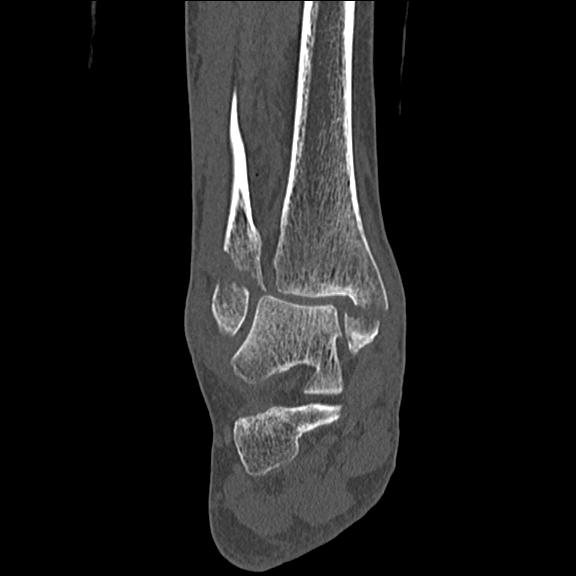

102755 1/4 2R 1/15 2R 右足関節 68歳女性 右三果脱臼骨折